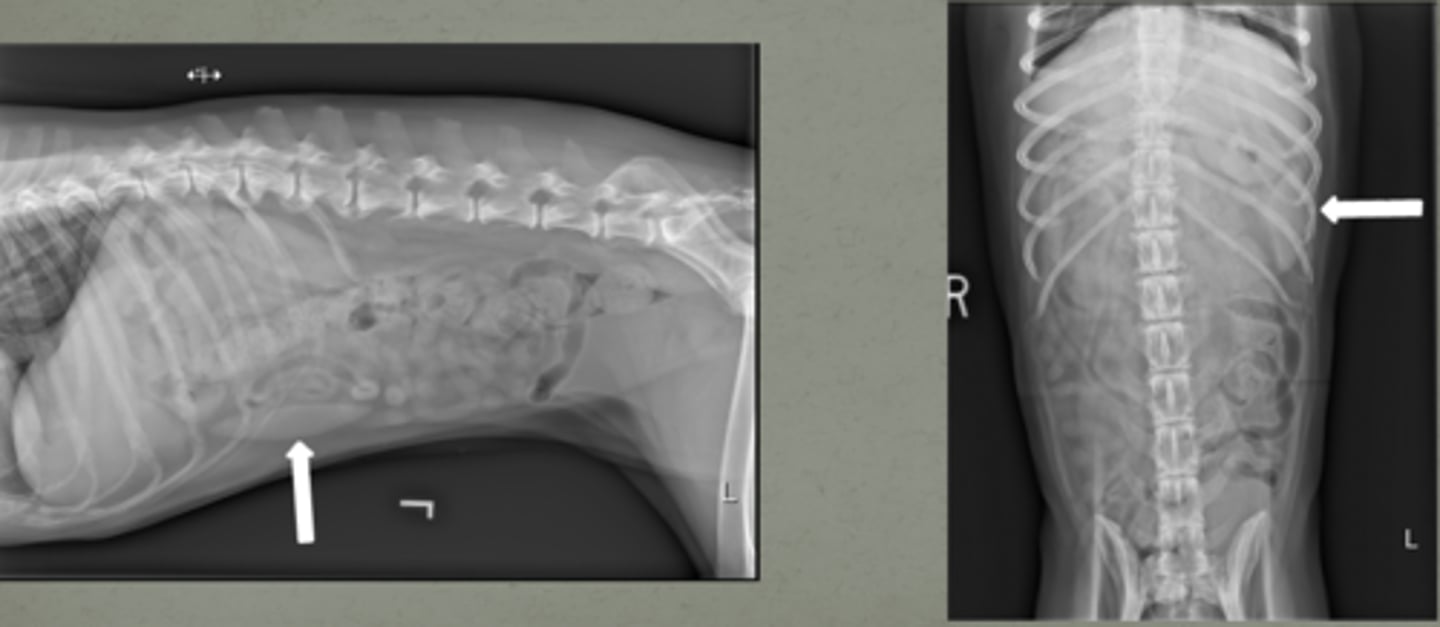

lateral and VD

large breed canine spleens can be seen on both _____ and _____ images

abnormal- enlarged

is this a normal or abnormal spleen?